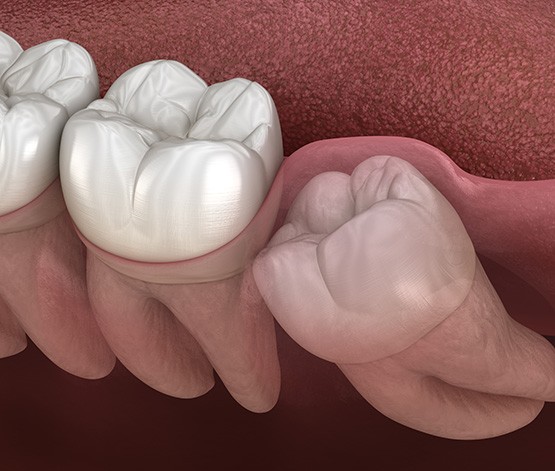

Removing wisdom teeth requires either a simple or surgical procedure. For those molars that have partially erupted and can be seen above the gumline, the use of dental forceps is often enough to move the teeth back and forth until they detach. However, if these teeth are impacted (beneath the gumline), it requires a more invasive procedure.

When a surgical approach is required, our on-staff oral surgeon will make a small incision in the gums after administering local anesthesia. Once the underlying tooth is exposed, it will be sectioned for easier removal. This prevents irritating the bone and makes for a more comfortable and successful procedure.